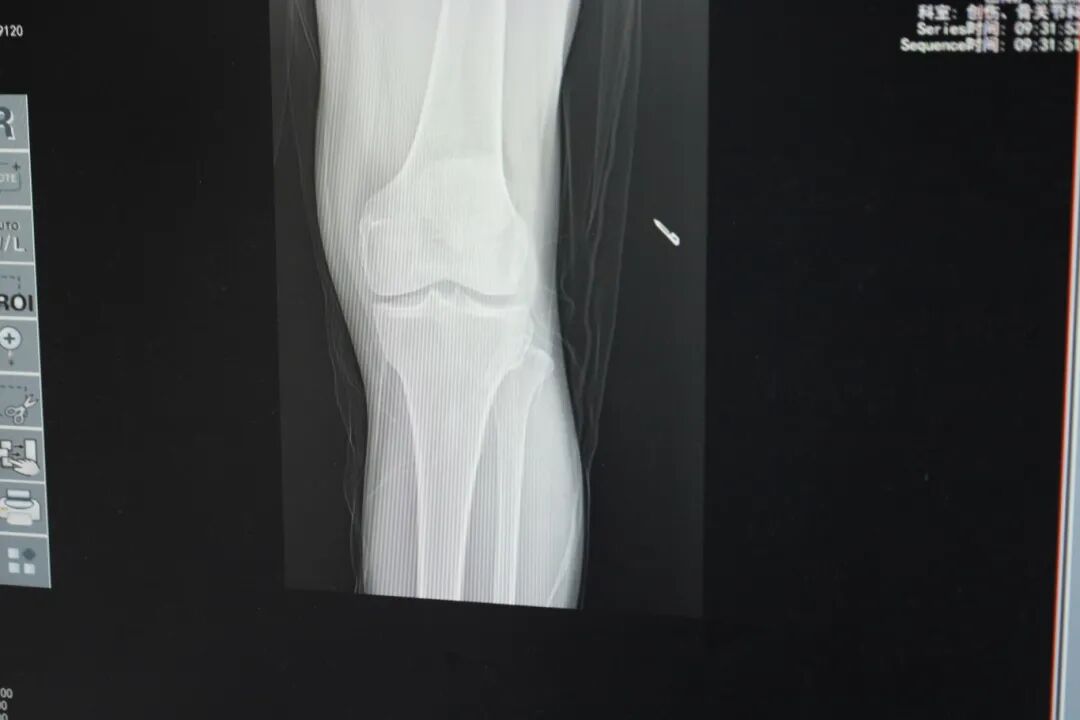

科室为参与的患者提供免费X线复查、关节功能评估、一对一康复指导及现场答疑,把专业医疗服务送到患者身边,用细致随访筑牢康复防线。